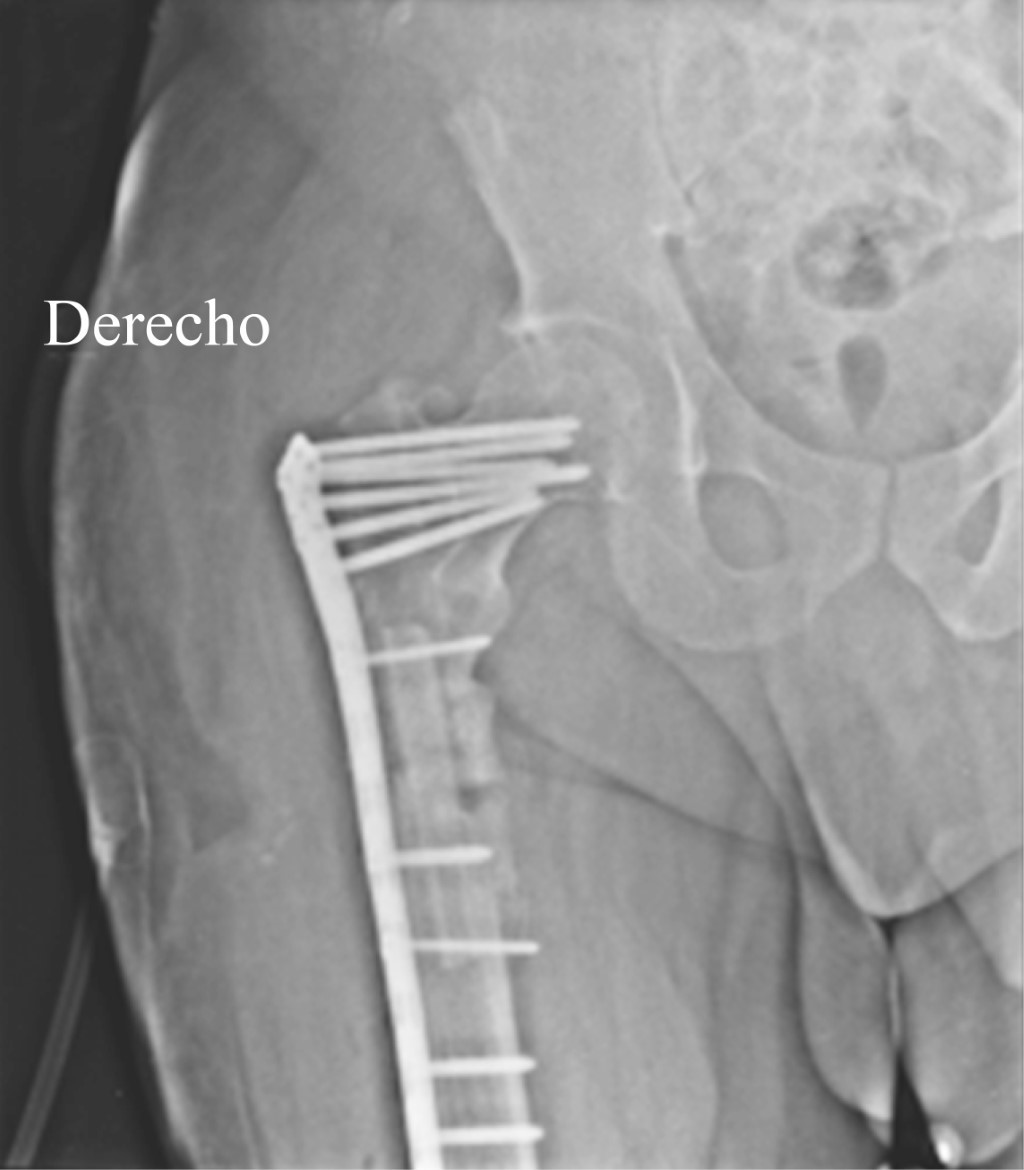

El paciente evolucionó adecuadamente, la herida quirúrgica cicatrizó por completo hasta el día de hoy con infección en remisión y evidencia radiológica de consolidación de la fractura, además paciente asintomático con función preservada de la extremidad (Figuras 7 y 8).

Figura 7